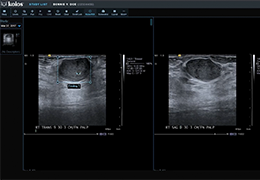

ART-Plan™ Artificial Intelligence Contouring